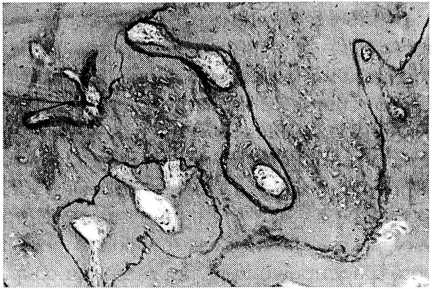

Рис. 2. Незрелая гетеротопическая кость. Видны отдельные линии склеивания извилистого характера.

При морфологическом исследовании гетеротопических оссификатов выявлена в основном незрелая новообразованная кость с неполноценной архитектоникой: пластинчатое строение отсутствует, каналы кости отличаются разнонаправленной ориентацией, остеоциты распределены неравномерно (рис. 1). Линии склеивания малочисленны, имеют неровный, ломаный характер, межклеточный матрикс кости окрашивается неравномерно (рис. 2), в межбалочных пространствах рыхлая клеточно-волокнистая ткань с избыточным содержанием сосудистых элементов. Поверхность кости неровная, часто обнаруживаются лакуны резорбции, содержащие остеокласты и гистиоциты. Вблизи новообразованной кости в элементах соединительнотканных волокон выявляются разрозненные, малодифференцированные клеточные элементы мезенхимального происхождения, которые, повидимому, постепенно превращаются в хрящевые и костные клетки, поскольку именно в этих участках наблюдается активное образование и обызвествление гетеротопической кости.